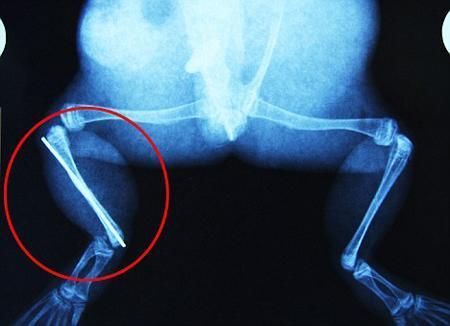

環(huán)球網(wǎng)4月2日?qǐng)?bào)道 據(jù)《每日郵報(bào)》報(bào)道,上個(gè)月,南非大牛蛙布魯萊的右小腿被鄰居家的一只狗咬到,導(dǎo)致粉碎性骨折,現(xiàn)在經(jīng)過(guò)2個(gè)小時(shí)的手術(shù),它的斷腿已經(jīng)被接上,它也因此成為有史以來(lái)第一只通過(guò)外科手術(shù)用鋼針接上斷腿的青蛙。

野生生物專(zhuān)家安妮經(jīng)常為學(xué)校寫(xiě)教材,她認(rèn)為這是人類(lèi)第一次通過(guò)手術(shù)給一只青蛙接斷腿。在手術(shù)開(kāi)始階段,獸醫(yī)把少量給狗用的麻醉藥注入到這只青蛙體內(nèi),讓它失去知覺(jué)。然后他在布魯萊的斷腿上切開(kāi)一個(gè)小口,把一根小鋼針植入腿里。最后獸醫(yī)給它縫了9針,把切口縫合在一起。僅僅幾周后,布魯萊就能在安妮家附近活動(dòng)了。這只青蛙大約已有25歲,主要以嚙齒動(dòng)物、蛇和其他青蛙為食。布魯萊所屬的牛蛙種群正在不斷減小,目前只能在非洲南部的濕地里才能看到這種青蛙。

安妮有2個(gè)孩子,她已經(jīng)從事20多年兩棲動(dòng)物保護(hù)工作。她認(rèn)為鄰居家的狗狗在把布魯萊從地下刨出來(lái)的時(shí)候,它正在地下冬眠、她說(shuō):“世界上只有這個(gè)地區(qū)能看到這種牛蛙,這種青蛙現(xiàn)在變得越來(lái)越稀少。因?yàn)槲覐氖乱吧锉Wo(hù)工作,因此認(rèn)識(shí)很多兩棲動(dòng)物專(zhuān)家,但是以前他們誰(shuí)也沒(méi)見(jiàn)過(guò)這種事情?吹讲剪斎R越來(lái)越健康我非常開(kāi)心,F(xiàn)在還需要一段時(shí)間,它的金屬腿和它的骨骼才能融為一體,那時(shí)布魯萊會(huì)跟以前一樣健康。我們認(rèn)為這個(gè)過(guò)程需要幾周時(shí)間,但是一旦它完全康復(fù),我希望把它放歸大自然,讓它重新回到它最鐘愛(ài)的濕地里。”